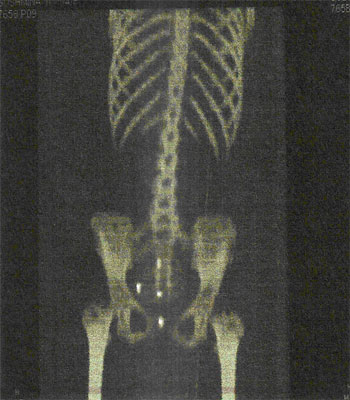

Ewing’s Sarcoma

INITIAL STAGE

10-Feb-2009

Before Treatment :

Scan findings consistent with multiple skeletal mets from Ewing’s Sarcoma.

X-Ray DURING HERBAL ONCOLOGY

01-Aug-2009

Absence of viable tumour

X-RAY AFTER HERBAL ONCOLOGY

04-Sep-2009

AfterTreatment :

No Focus abnormally increased FDG uptake to suggest metabolically active disease on the present study